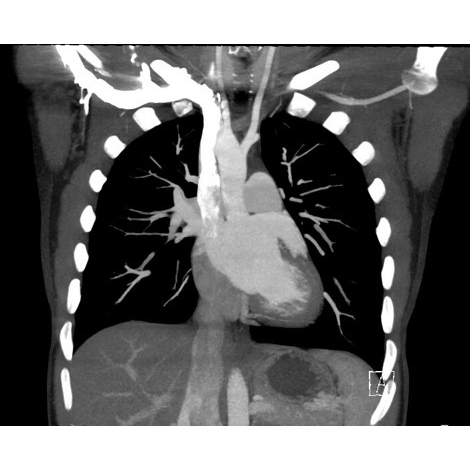

Two-view chest X-ray: Right-sided aortic arch noted Case Photo #1 .